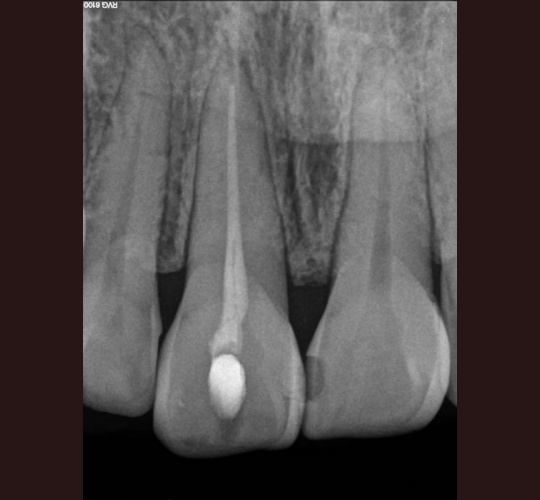

Internal Bleaching: Case #3

Posted in Internal Bleaching